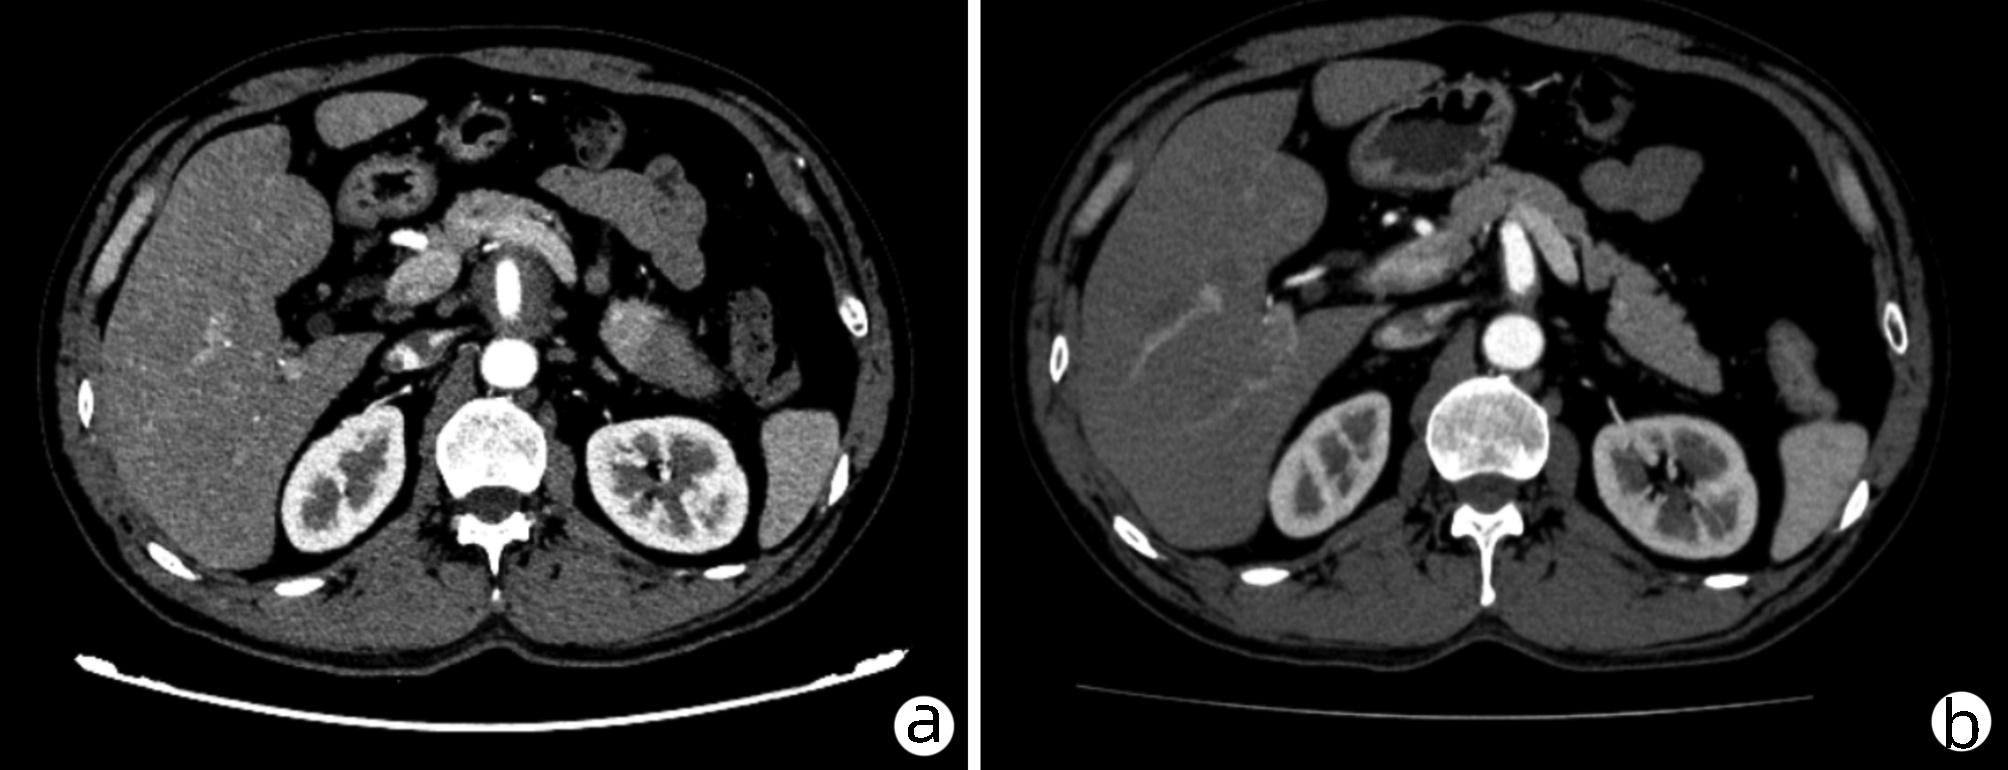

目的  评价在慢性乙型肝炎患者腹部CT中通过测量胸、腰椎CT值,诊断骨量减少/骨质疏松的诊断价值。分析慢性乙型肝炎患者发生骨量减少/骨质疏松的危险因素。  方法  回顾性纳入2019年1月—2020年12月在昆明医科大学第二附属医院就诊的慢性乙型肝炎患者112例,所有患者均完善了腹部CT检查,部分患者完善了双能X线骨密度测定(DXA)。测量T12椎体至L3椎体的CT值,分析每一椎体CT值与DXA检查基于L1~L4椎体测得的T-score值相比诊断骨量减少/骨质疏松的诊断价值。以椎体CT值为诊断标准,将纳入的慢性乙型肝炎患者分为骨量减少/骨质疏松组(n=55)与骨量正常组(n=57),对比两组患者临床特征、生化指标,分析慢性乙型肝炎患者发生骨量减少/骨质疏松的危险因素。符合正态分布的计量资料两组间比较采用t检验;非正态分布的计量资料两组间比较采用Mann-Whitney U检验。计数资料组间比较采用χ2检验、Fisher确切检验、Bonferroni校正检验。相关性采用Pearson相关分析。多因素分析采用二元logistic回归分析。根据受试者工作特征曲线(ROC曲线)评估T12~L3椎体CT值诊断慢性乙型肝炎患者合并骨量减少/骨质疏松的诊断价值。一致性检验采用Kappa检验。  结果  分析46例在同次住院中完善了腹部CT和DXA检查患者的T12~L3椎体CT值,均分别与DXA检查结果中基于L1~L4椎体计算的T-score值有显著正相关性(rT12=0.694,rL1=0.661,rL2=0.781,rL3=0.685,P值均<0.001);经ROC曲线分析,L2椎体CT值ROC曲线下面积最大(0.863),诊断骨量减少/骨质疏松具有较好准确性,与DXA检查结果具有较好一致性(K=0.648,P<0.001)。分析112例慢性乙型肝炎患者临床特征、生化指标,提示高龄(比值比为1.108,95%CI:1.026~1.196,P=0.009)、合并肌少症(比值比为2.788,95%CI:1.009~7.707,P=0.048) 是骨量减少/骨质疏松发生的危险因素。  结论  慢性乙型肝炎患者常需定期复查腹部CT评估肝脏疾病进展情况,通过测量患者腹部CT图像中L2椎体CT值、L3椎体层面骨骼肌面积筛查是否存在骨量减少/骨质疏松、肌少症,及时干预,提高患者的预后、生活质量,具有较高临床意义。